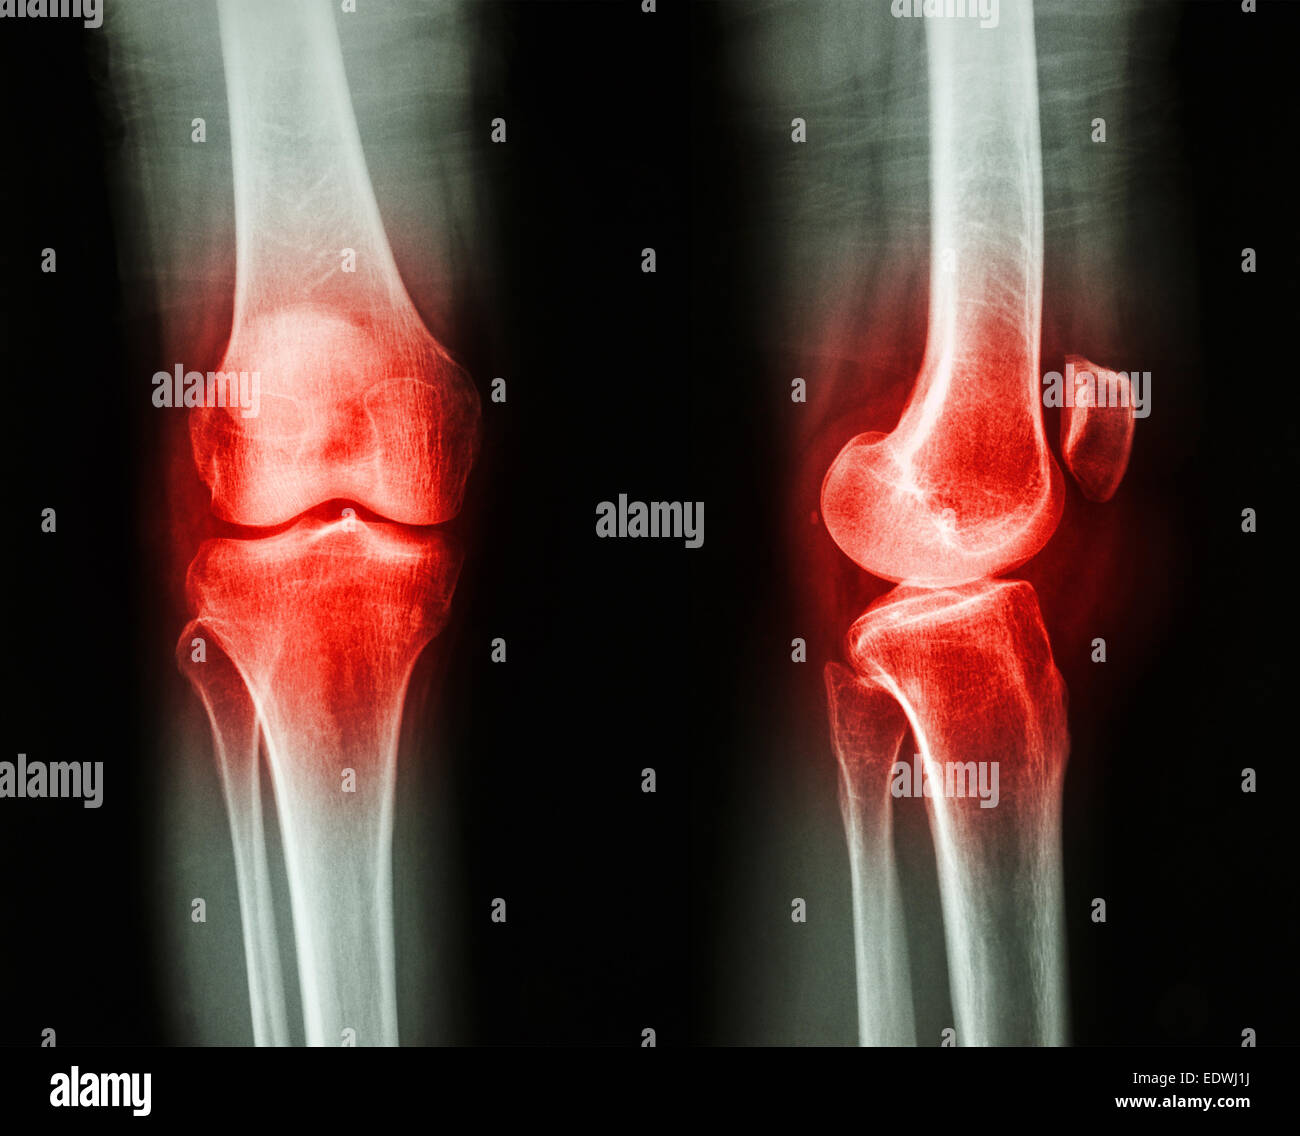

Film x-ray AP/GENOU Arthrose : latéral (Inflammation au genou) Banque D'Imageshttps://www.alamyimages.fr/image-license-details/?v=1https://www.alamyimages.fr/photo-image-film-x-ray-ap-genou-arthrose-lateral-inflammation-au-genou-77394958.html

Film x-ray AP/GENOU Arthrose : latéral (Inflammation au genou) Banque D'Imageshttps://www.alamyimages.fr/image-license-details/?v=1https://www.alamyimages.fr/photo-image-film-x-ray-ap-genou-arthrose-lateral-inflammation-au-genou-77394958.htmlRFEDWJ1J–Film x-ray AP/GENOU Arthrose : latéral (Inflammation au genou)

Film x-ray AP/GENOU Arthrose : latéral (Inflammation au genou) Banque D'Imageshttps://www.alamyimages.fr/image-license-details/?v=1https://www.alamyimages.fr/photo-image-film-x-ray-ap-genou-arthrose-lateral-inflammation-au-genou-77394956.html

Film x-ray AP/GENOU Arthrose : latéral (Inflammation au genou) Banque D'Imageshttps://www.alamyimages.fr/image-license-details/?v=1https://www.alamyimages.fr/photo-image-film-x-ray-ap-genou-arthrose-lateral-inflammation-au-genou-77394956.htmlRFEDWJ1G–Film x-ray AP/GENOU Arthrose : latéral (Inflammation au genou)